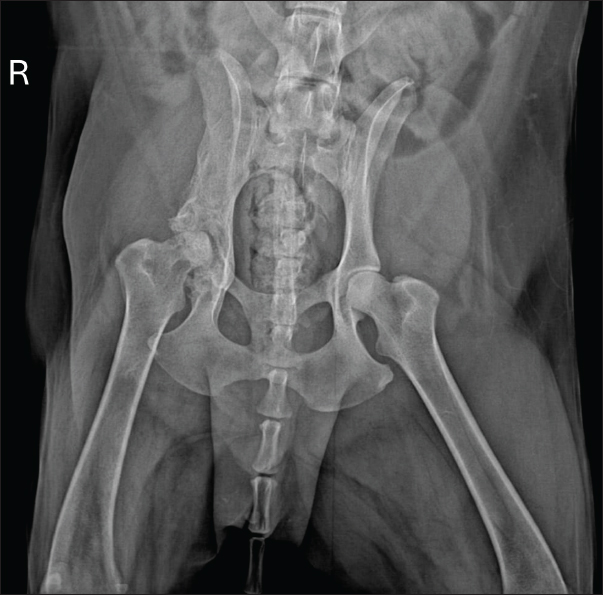

Based on clinical and radiographic improvement, itraconazole and gabapentin were continued for an additional 30 days, while cephalexin was discontinued to minimize potential adverse effects. After 60 days of treatment, follow-up radiographs demonstrated continued gradual reduction in osteolysis (Fig. 5). Therapy was extended for an additional 3 months, with ongoing clinical improvement.

Fig. 5. Radiographic examination of the dog 60 days after initiation of itraconazole treatment, showing ongoing, albeit slight, reduction of osteolytic areas.